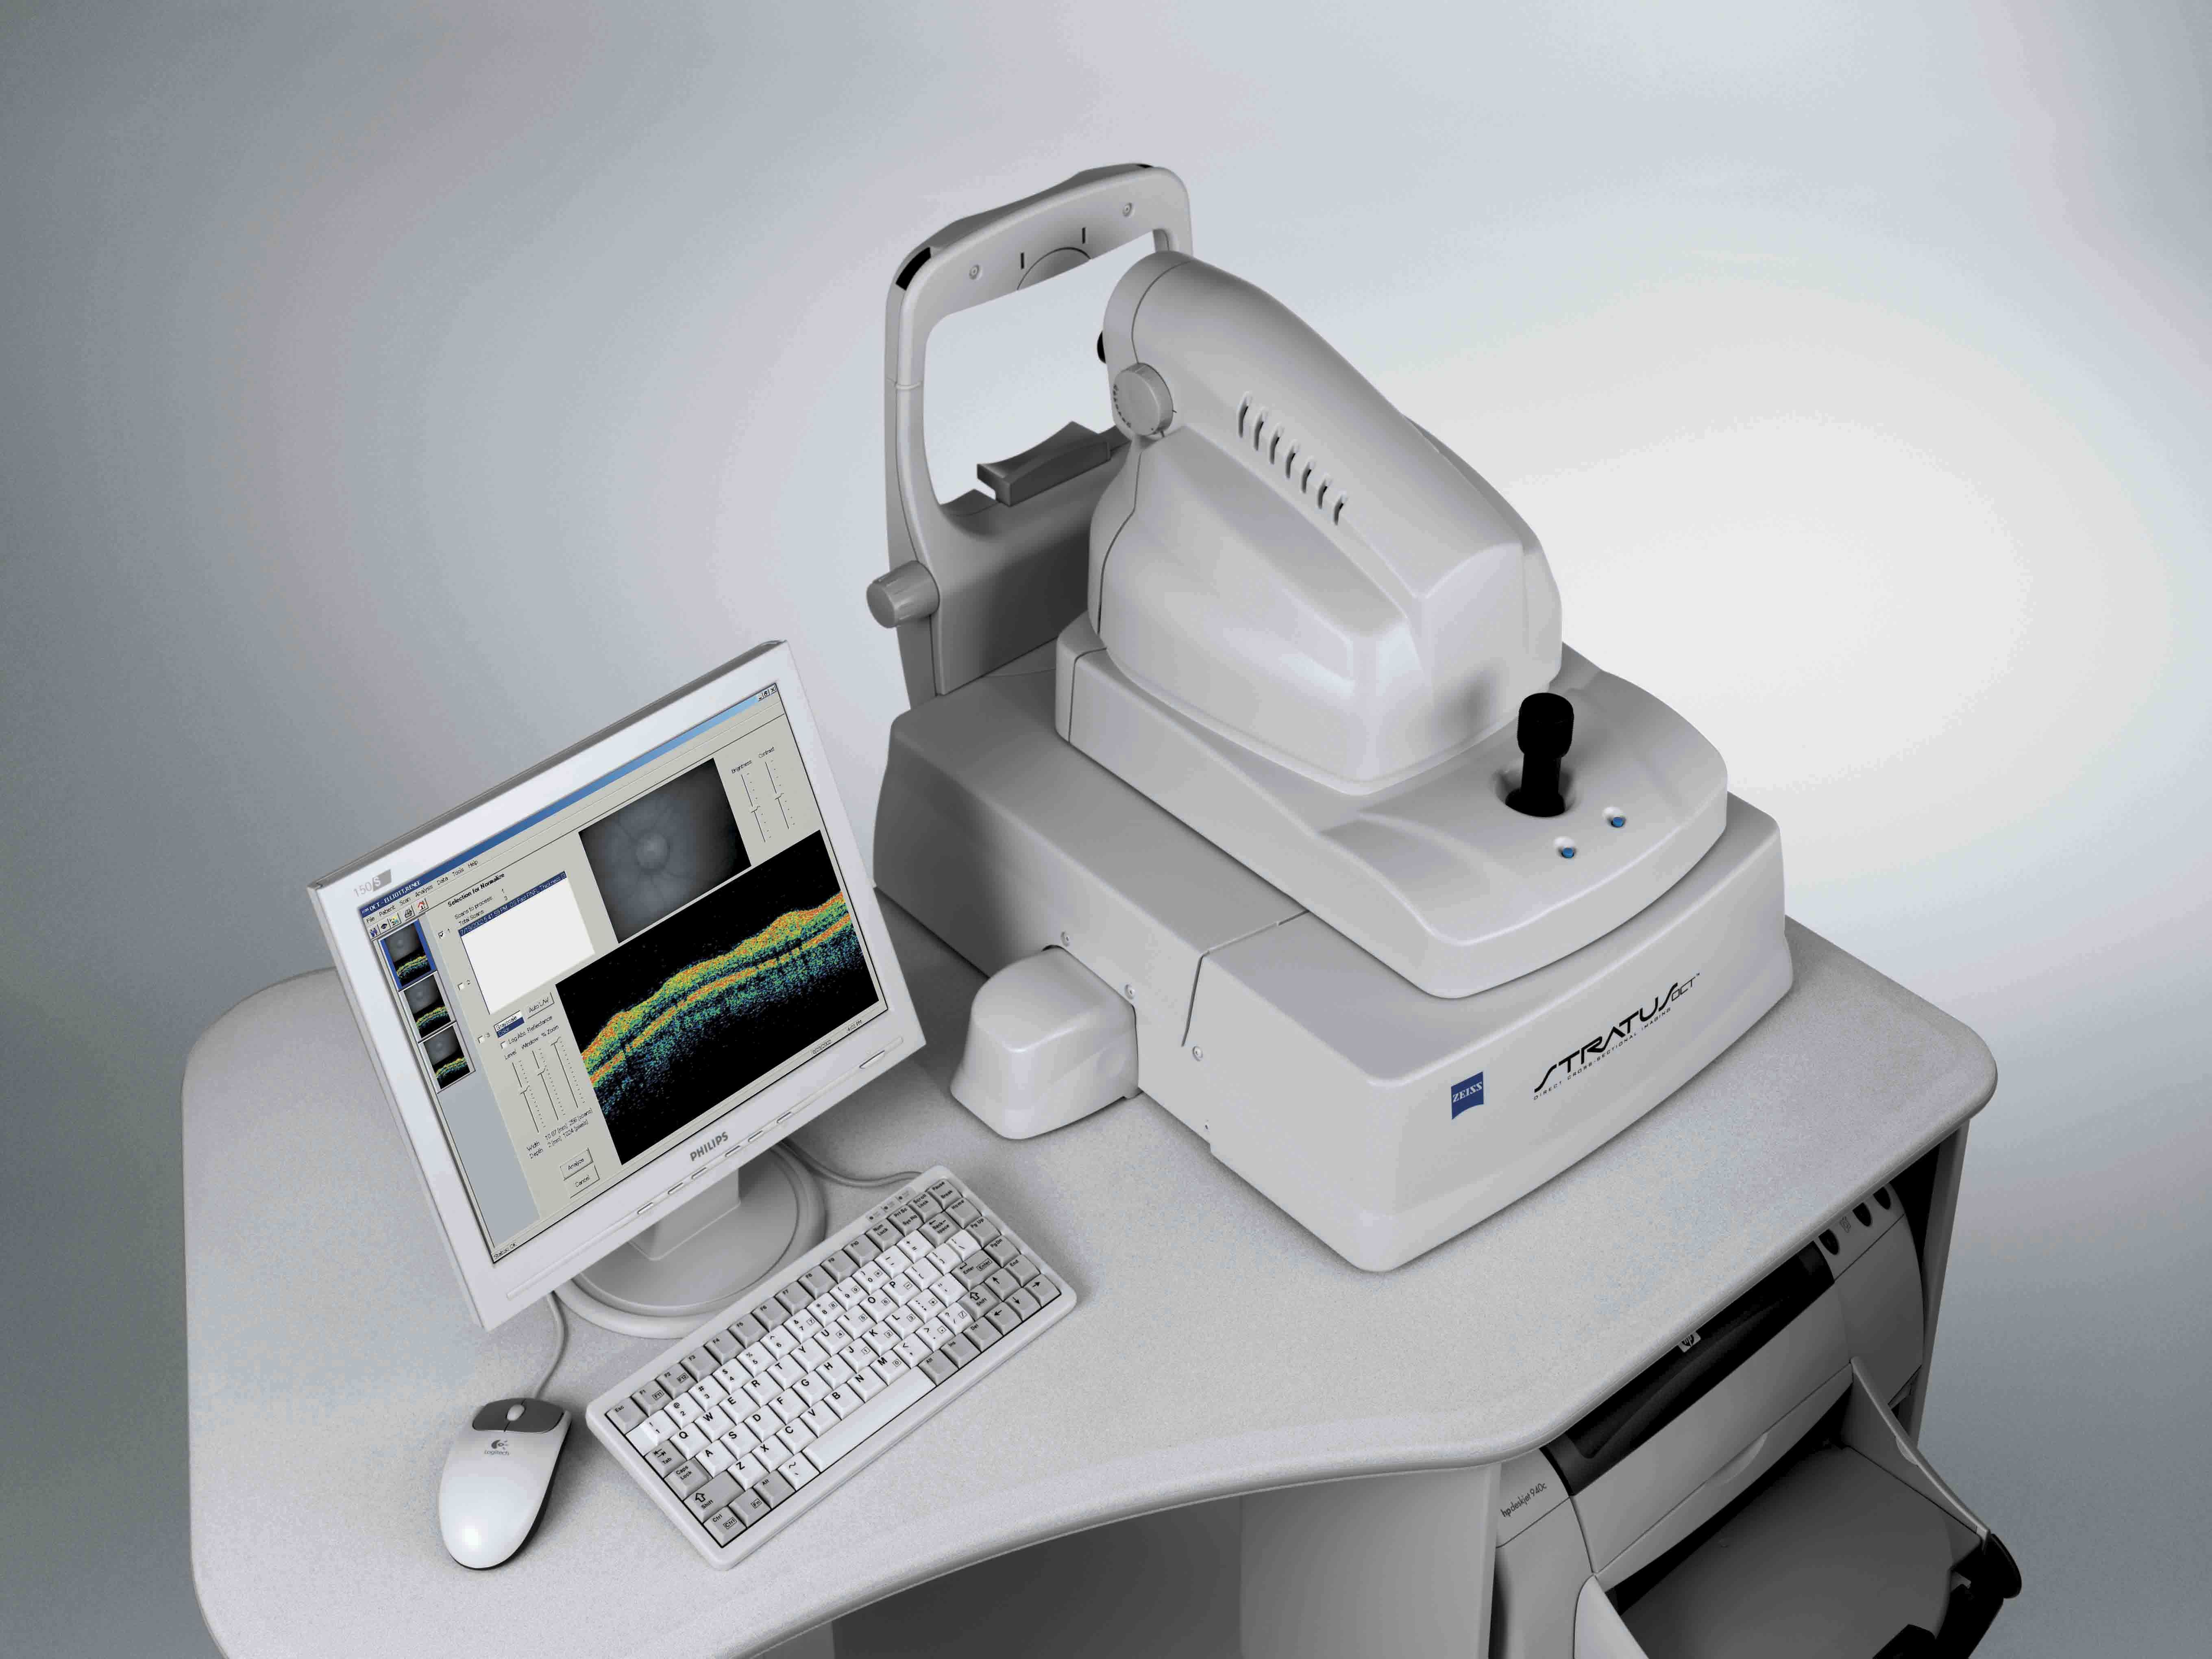

La tomografia a coerenza ottica (OCT) è un test di imaging non invasivo che utilizza le onde di luce per scattare foto della retina, e in particolare della macula. La macula è una parte della retina deputata alla visione a colori e ad alta definizione.

Con l’OCT possono essere analizzati e mappati tutti gli strati retinici, inoltre è possibile rilevare lo spessore retinico. Questi dati aiutano a effettuare una corretta diagnosi e a fornire delle indicazioni per il trattamento del glaucoma e delle patologie retiniche, malattie come la degenerazione maculare senile e la retinopatia diabetica.